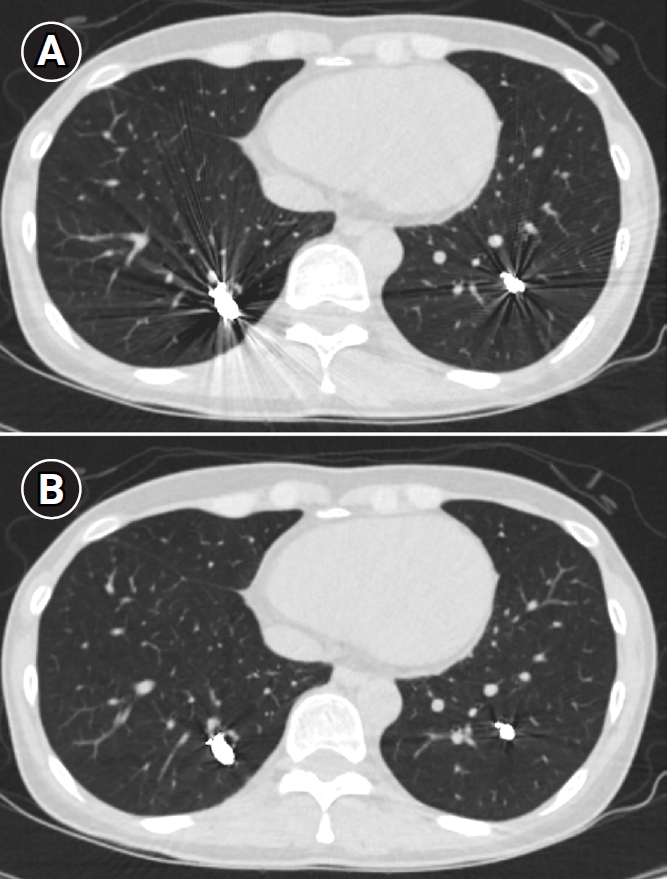

Fig. 9.

Computed tomographic images of a patient with bilateral lower lobe pulmonary arteriovenous malformations treated with coil embolization. (A) Image without metal artifact reduction, showing prominent beam-hardening artifacts that obscure the evaluation of surrounding vessels and parenchyma. (B) Image with metal artifact reduction technique applied, significantly reducing beam-hardening artifacts and allowing for better evaluation of the adjacent vessels and parenchyma.

Fig. 9. Computed tomographic images of a patient with bilateral lower lobe pulmonary arteriovenous malformations treated with coil embolization. (A) Image without metal artifact reduction, showing prominent beam-hardening artifacts that obscure the evaluation of surrounding vessels and parenchyma. (B) Image with metal artifact reduction technique applied, significantly reducing beam-hardening artifacts and allowing for better evaluation of the adjacent vessels and parenchyma.

Long-term follow-up after treating PAVMs is needed to detect newly developed PAVMs and to identify persistence or recurrent flow [10,11]. Treatment failure in PAVMs can be classified as recanalization and reperfusion. Recanalization refers to the reopening of blood flow through spaces between the previously placed embolic material (Fig. 6). Reperfusion, on the other hand, occurs when blood flow from an adjacent pulmonary artery reopens the previously embolized distal vein or venous sac (Fig. 7) [32]. As the primary follow-up modality, CT is recommended, but there are currently no specific guidelines on whether or not to use contrast enhancement [33]. It is recommended to perform an initial evaluation by CT about 6 months after PAVM embolization, and then follow-up with CT every 3–5 years thereafter (Fig. 8). In CT follow-up, the evaluation is based on the reduction rate of the venous sac or the draining vein, and the traditional criterion is that there should be at least a 70% reduction in the size of the venous sac or draining vein [34,35]. In recent studies, there have been opinions that this 70% size reduction criterion is too strict. In response, some research using angiographic-confirmed cases or time-resolved magnetic resonance angiography (TR-MRA) has proposed a 50%–60% guideline [36,37]. When using CT, repeated radiation exposure and metal artifacts from the coils can be problematic. By using metal artifact reduction techniques, it is possible to obtain clear images of the surrounding parenchyma, and this also helps in assessing parameters like the draining vein diameter reduction rate (Fig. 9) [38]. Furthermore, low-dose CT protocols may help reduce cumulative radiation exposure during repeated follow-up imaging.